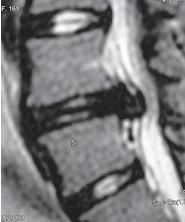

Для того чтобы вы лучше понимали ответственный труд хирургов, немного разбирались в вопросах и проблемах, связанных с результатами хирургического лечения, приведу из своего документального медицинского архива несколько показательных снимков МРТ из истории болезни пациентов до того, как они посетили мою клинику. Естественно, ни фамилии данных пациентов, ни фамилии оперировавших их хирургов не указываю из этических соображений. Уверен, что данные снимки будут интересны как пациентам, так и специалистам, практикующим в области вертебрологии.

МРТ № 97

На МРТ № 97 у шестнадцатилетней пациентки наблюдается секвестрированная грыжа межпозвонкового диска в сегменте LIV-LV.